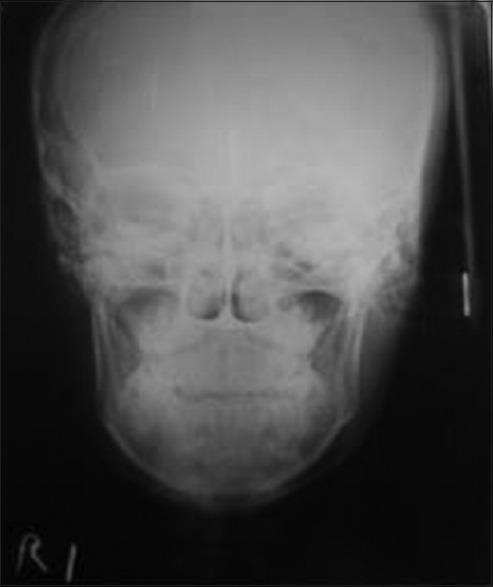

Unilateral condylar hyperplasia is an uncommon condition with unknown etiology which causes overdevelopment of condyle leading to facial asymmetry, mandibular deviation, malocclusion, and articulation dysfunction. Two Indian families with unilateral condylar hyperplasia are presented where the similar abnormality was also detected in one of their parents. The condylar hyperplasia in these two families indicates that mandibular condylar hyperplasia could be genetic in origin.

单侧髁突增生是一种病因不明的罕见病症,它会导致髁突过度发育,进而引起面部不对称、下颌偏斜、错牙合畸形及关节功能障碍。本文报告了两个患有单侧髁突增生的印度家族,在他们的一位家长中也检测到了类似异常。这两个家族中的髁突增生表明下颌髁突增生可能起源于遗传。